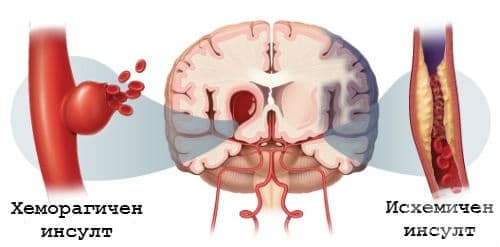

Диагнозата и диференциалната диагноза на отделните форми на остри исхемични нарушения на мозъчното кръвообращение. Те се базират на клиничната картина, невроизобразяващите изследвания - компютърна томография (КТ) и магнитно-резонансна томография (МРТ), ултразвуковите изследвания, като доплерова сонография (УДС), ангиография, ликворно изследване и изследване на очните дъна. За уточняване на причината на инфаркта се изследват още протеин "С", антикардиолипинови антитела, С-реактивен протеин, хомоцистеин и други.

Диференциална диагноза на инсулт се прави с интрацеребрална хеморагия, субарахноидна хеморагия и заболявания като: